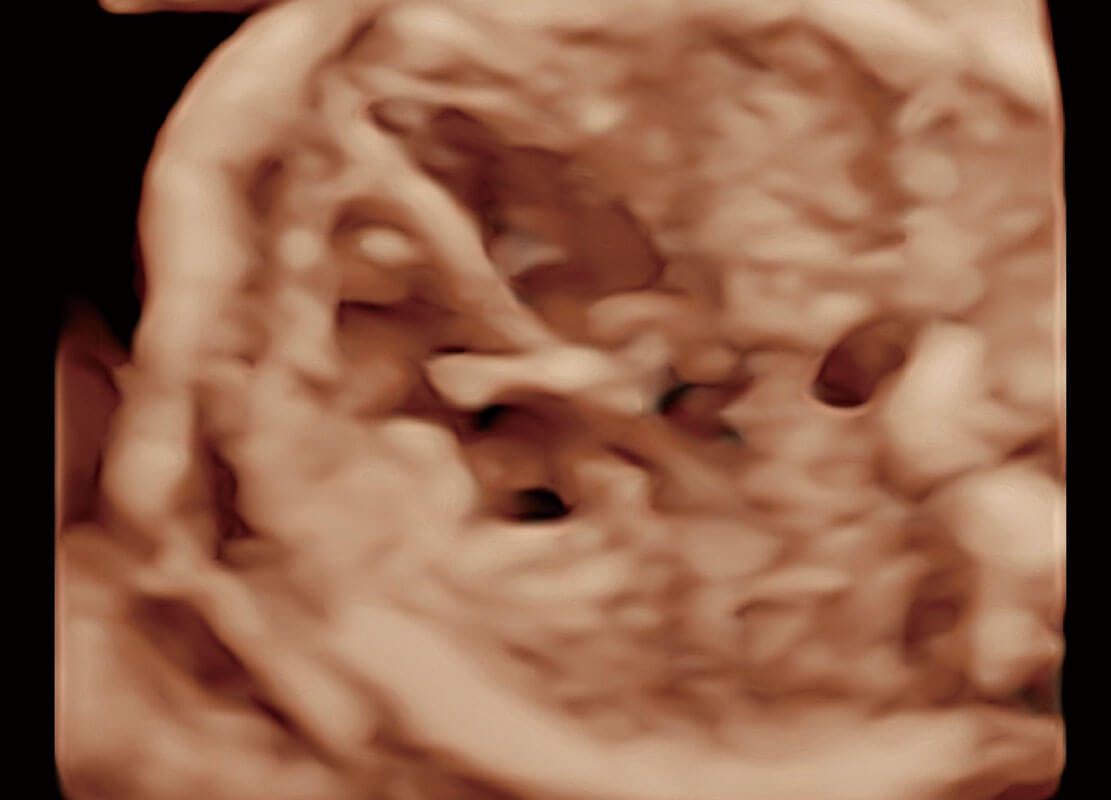

胎心筛查

P60搭载一系列胎儿心脏成像技术,实现精细的胎儿心脏评估。

• 四腔切面

• 四腔心血流

• 右室双出口

• 胎心容积成像